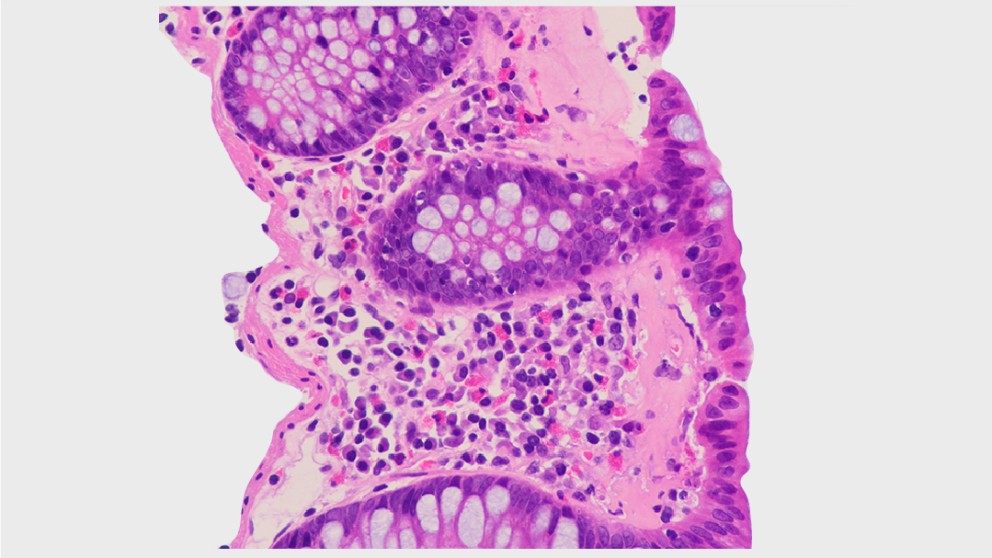

Microscopic colitis is an inflammatory bowel disease (IBD) that leads to chronic, watery diarrhoea. First believed to be rare, microscopic colitis has received more attention in recent decades, resulting in increasing incidence rates that exceed those of classic IBD in some countries. Hopefully, it is common practice nowadays to refer patients with chronic diarrhoea for a colonoscopy with biopsy samples taken, as this is the only way to diagnose microscopic colitis. Histology results distinguish between the subtypes of microscopic colitis — lymphocytic colitis, collagenous colitis and the more recently introduced incomplete microscopic colitis.